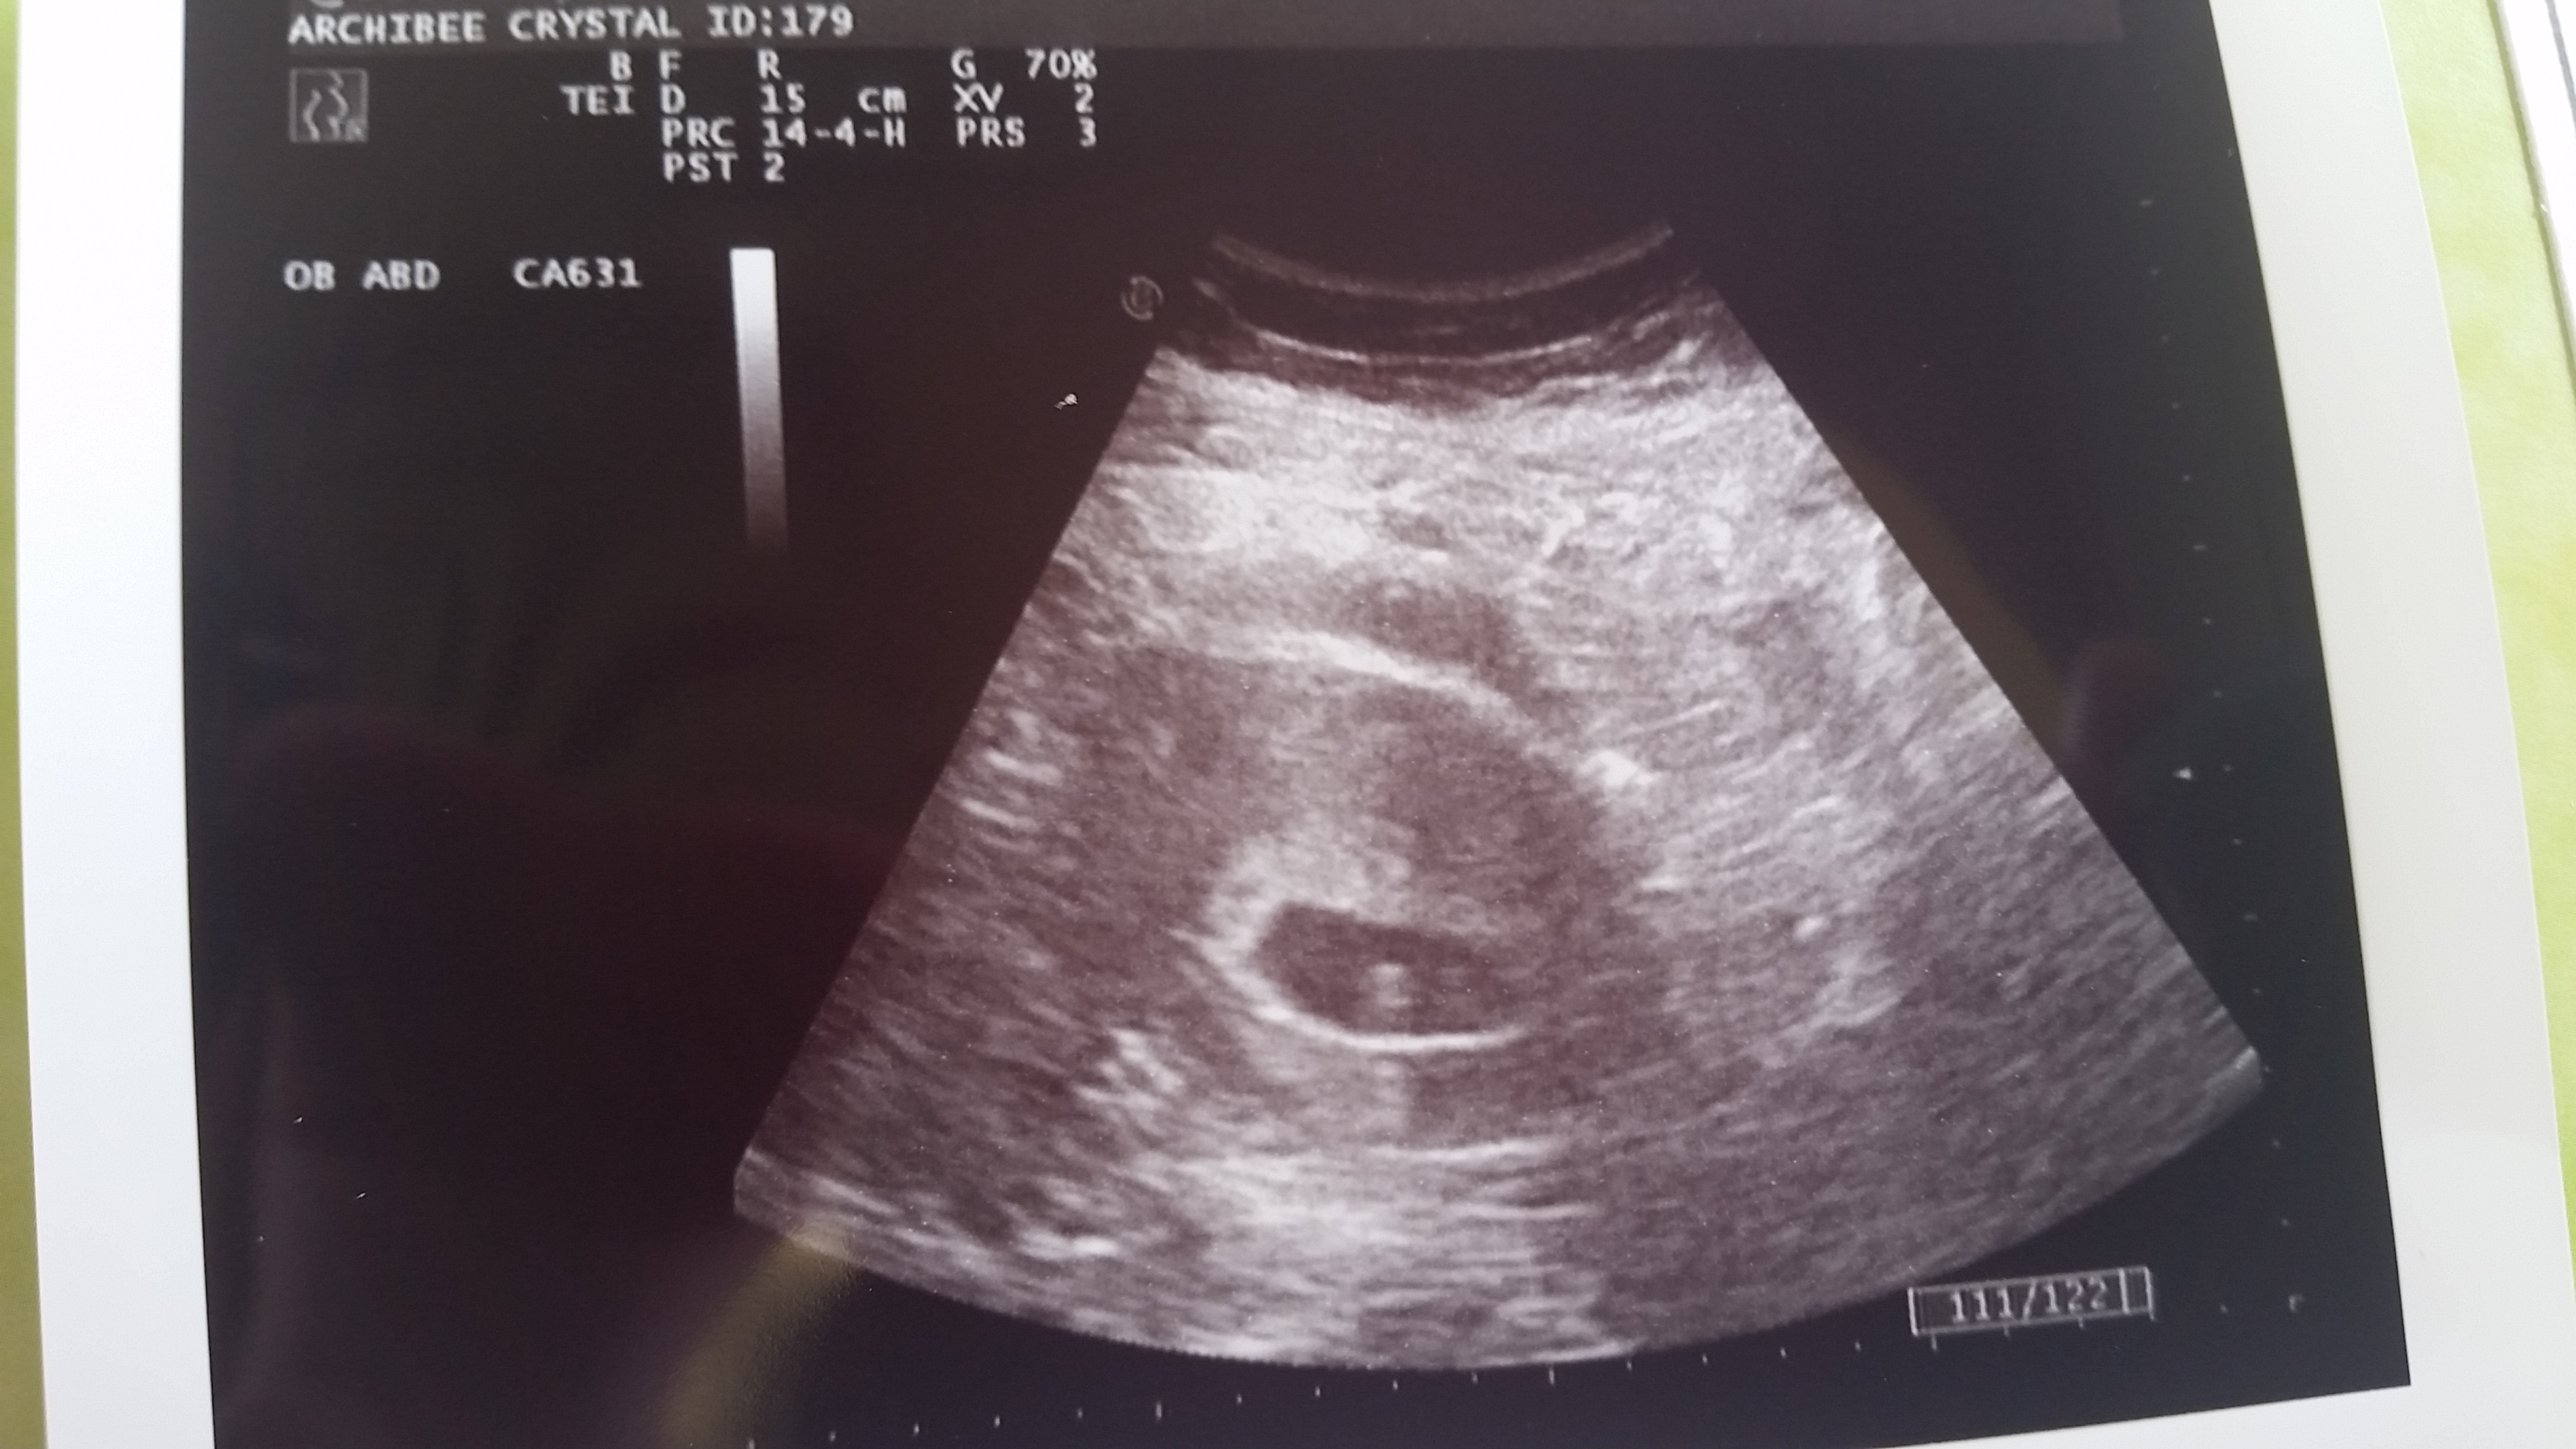

Web ultrasound pictures showcase different colors depending on how the sound waves bounce off of the substance. It may be used to check for a number of conditions. Web today, you can view parts of your electronic health records (ehrs) online, including radiology reports and images. For liquid substances like amniotic fluid, the picture. The hospitals use the numbers and.

It’s not very complicated but requires attention and understanding. You need to understand that white is solid and black is liquid. Be aware that ultrasound does. The very top is where the probe rests, so the image shows what the organs and fetus look like from the side, not the top. This understanding will make it easier for you to.

Web citation, doi, disclosures and article data. For solid substances like bones, the picture will appear white. Web open dicom files with a free viewer. Be aware that ultrasound does. Color an ultrasound or sonogram picture is a black and white photograph, so they all look the same to someone who doesn't know much about how to read an ultrasound.